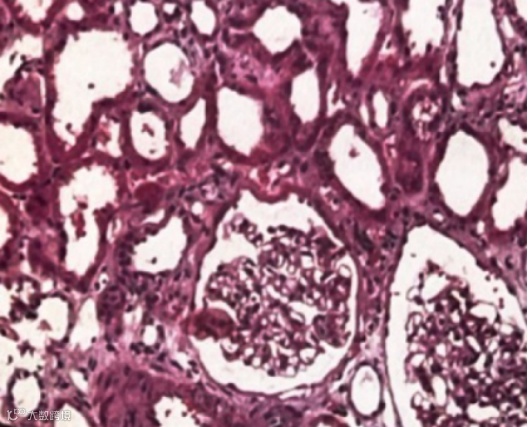

甲状旁腺肿物切除术后第2天行肾穿刺。免疫荧光:免疫球蛋白和补体均阴性。光镜:13个肾小球无明显病变,肾小管多灶状萎缩,部分上皮细胞钙化。肾间质多灶状纤维化及钙化,小动脉无变化(图1)。电镜:可见肾小管上皮细胞内有钙颗粒。钙特殊染色阳性。

图1. 高钙肾病:肾小球无明显病变,肾小管上皮刷毛缘脱落,管腔扩张,肾间质轻度水肿(HE×200)